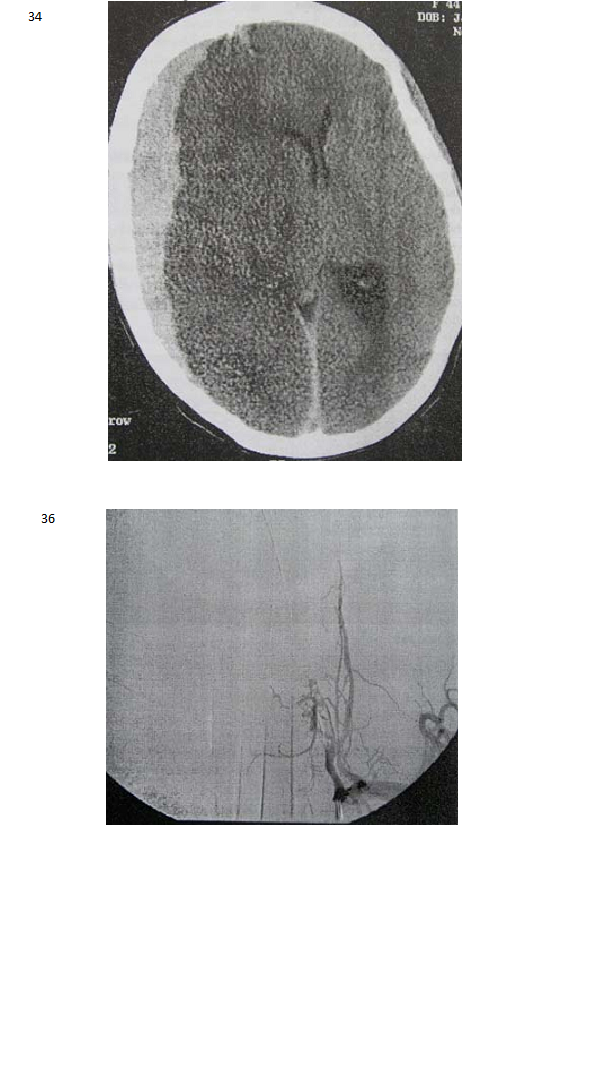

Seorang perempuan usia 54 tahun dibawa ke ruang gawat darurat setelah jatuh pingsan saat bekerja . Dia tersadar dan dapat berko-munikasi, dengan sakit kepala berat, fotopobia, nuchal kaku dan pandangan buram. CT atas otak mengungkapkan adanya darah subaraknoid menyebar pada cistern basal, Hidrosepalus ringan dan tidak tampak hematoma intraparenkimal. Angiogram pasien tampak pada Gambar.

Skenario: Laki-laki berusia 45 tahun dibawa ke ruang gawat darurat dalam keadaan demam, mual, muntah, dan sakit kepala hebat. Lumbar puncture mengungkapkan sel-sel darah merah sedikit

mengalami kenaikan, tapi jumlah protein, glukosa dan sel darah putih semuanya normal, termasuk tidak santokromia. Angiogram pasien tampak di bawah ini..

37. Manakah diantara etiologi di bawah ini yang merupakan etiologi yang paling mungkin merupakan etiologi dari kelainan yang ditunjukkan pada angiogram tersebut.?

A. Trauma kepala

B. Infeksi

C. Pradisposisi genetika

D. Penyakit vaskular kolagen